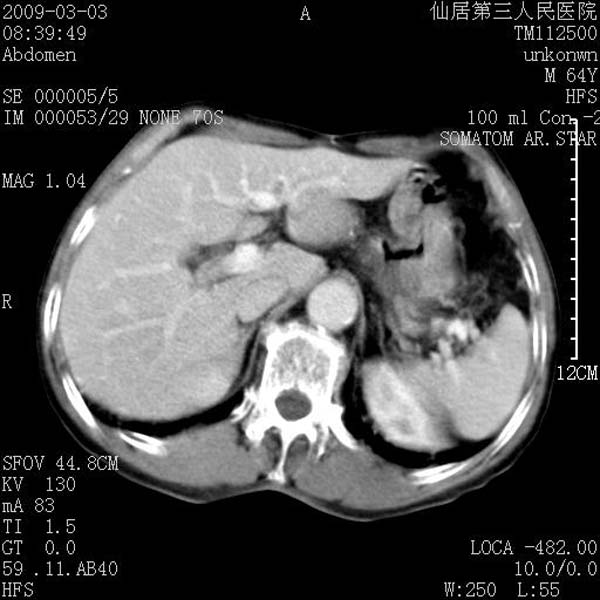

标题: CT18469:男性,64y,体检B超示肝脏低回声肿块,有胃溃疡手术 [打印本页]

患者,男性,64y,体检b超示肝脏低回声肿块,有胃溃疡手术史。

考虑----胃肠道间质瘤可能性大

从平扫及增强的特点来看,支持肝脏腺瘤并出血。

考虑胃间质瘤可能性大。

胃肠道间质瘤!

ct值呢?感觉没强化,象囊性。

考虑肝静脉韧带裂区良性占位性病变(囊肿?)。

考虑肝囊肿并出血可能性大.

考虑高密度囊肿可能性大